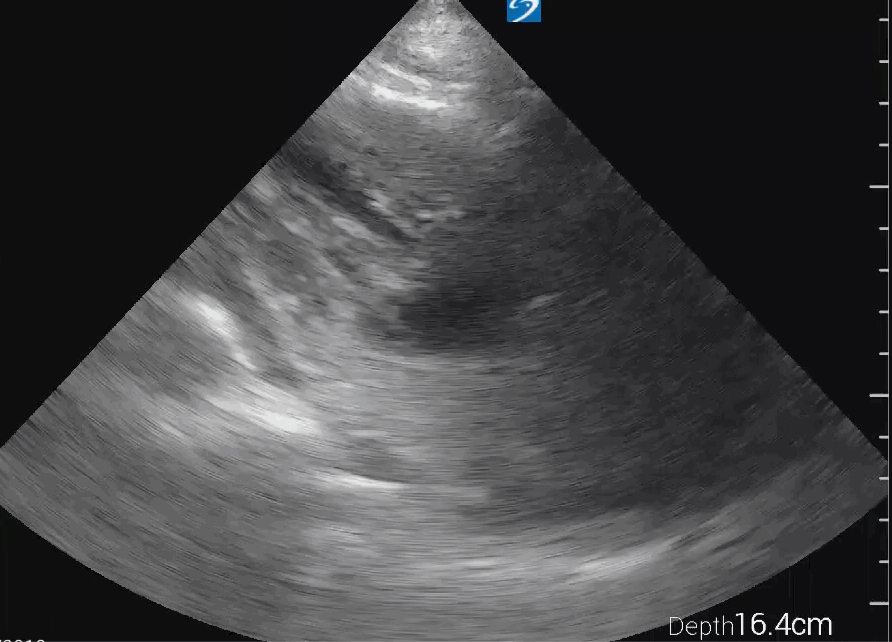

SC view

SC view of an empty left ventricle with severe hypertrophy: SC view from the same patient confirms the findings seen in the PLAX view. The left ventricle appears empty with severe hypertrophy, and muscular activity is present, indicating ongoing resuscitation efforts and the need to address the hypovolemic state. The small rim of pericardial effusion is also visible in this view, reinforcing the need for evaluation to determine if emergency drainage is warranted.